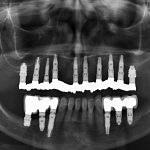

Figure 1. Diagram representing the measurements of the implant and crown to the posterior calculation of the CI ratio: The crown was measured from the highest cuspid of molars and premolars occlusal side, to the top of the implant platform, along a perpendicular line. The implant was measured at the centre, from the platform to the end of the apex

The crown-implant ratio was determined by two measurements: the crown was measured from the tip of the highest cusp to the platform of the implant, along a perpendicular line. The implant was then measured at the centre, from the platform to the end of the apex (Figure 1).